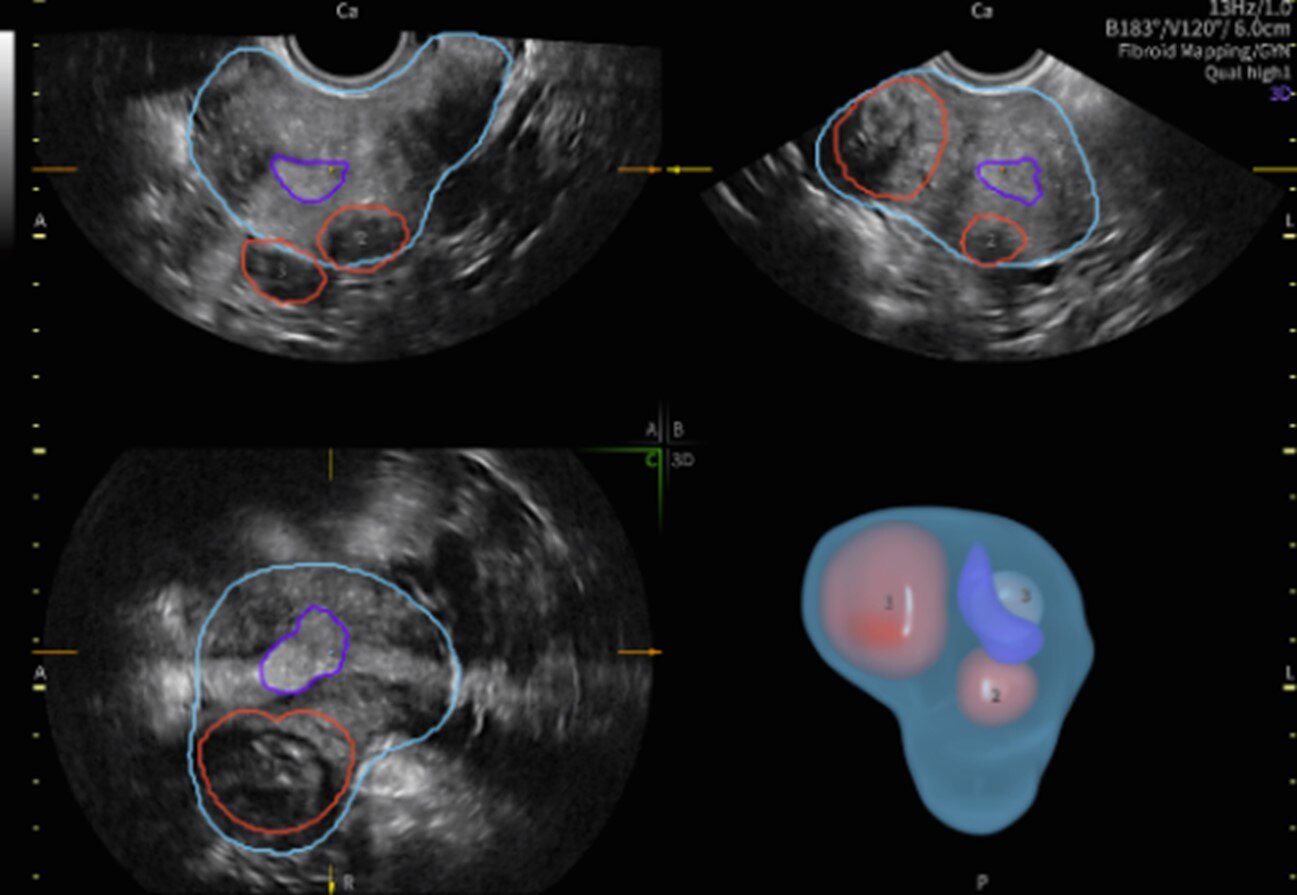

【画像】子宮筋腫と子宮、子宮内膜との位置関係を立体表示するFibroid Mappingは、医師同士や患者様とのコミュニケーション円滑化につながる